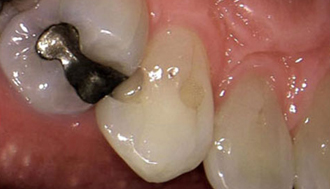

Zirconia Crowns:

For durable and aesthetically pleasing dental restorations, werecommend Zirconia Crowns, a type of tooth restoration treatment that covers severe decay and bad discoloration. Zirconia is a strong and biocompatible material that closely resembles the natural appearance of teeth. Our dental experts craft zirconia crowns with precision and artistry, ensuring a perfect fit and a seamless blend with your existing teeth. With zirconia crowns, you can achieve strong teeth and a pleasant smile.

Painless Root Canal Treatment:

At Venkateshwar Hospital,Delhi, painless root canal treatment is performed with precision and care. Using advanced local anesthesia techniques, we ensure minimal discomfort during the procedure. The dentist gently removes the infected pulp, cleans the canal, and seals it with biocompatible materials. Our modern equipment and experienced practitioners ensure efficient and virtually pain-free treatment. Patients can resume normal activities shortly after the procedure, experiencing relief from the initial pain caused by the infection.